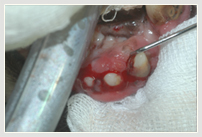

Parodontalerkrankung hochgradig! Extraktion der hochgradig

erkrankten Zähne